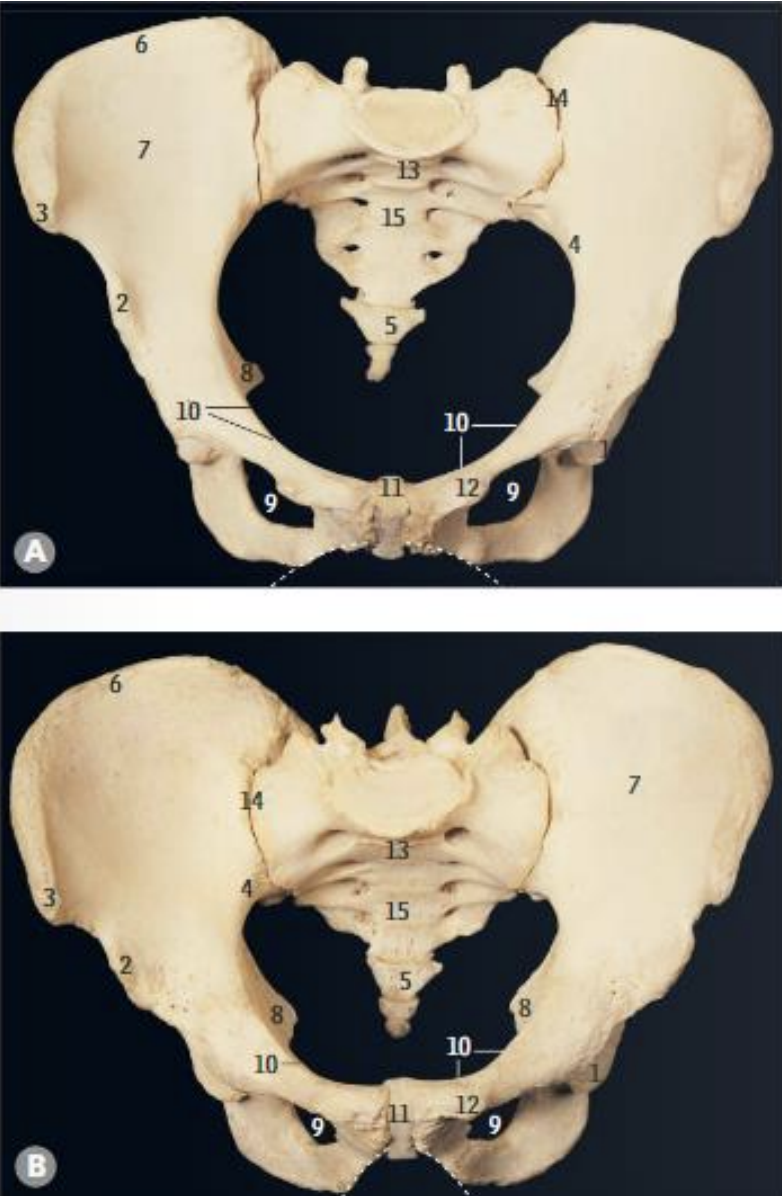

<p>What is structure 1?</p>

What is structure 1?

Acetabulum

<p>What is structure 2?</p>

What is structure 2?

AIIS

<p>What is structure 3?</p>

What is structure 3?

ASIS

<p>What is structure 4?</p>

What is structure 4?

Arcuate line

<p>What is structure 5?</p>

What is structure 5?

Coccyx

<p>What is structure 6?</p>

What is structure 6?

Iliac crest

<p>What is structure 7?</p>

What is structure 7?

Iliac fossa

<p>What is structure 8?</p>

What is structure 8?

Ischial spine

<p>What is structure 9?</p>

What is structure 9?

Obturator foramen

<p>What is structure 10?</p>

What is structure 10?

Pectineal line

<p>What is structure 11?</p>

What is structure 11?

Pubic symphysis

<p>What is structure 12?</p>

What is structure 12?

Pubic tubercle

<p>What is structure 13?</p>

What is structure 13?

Sacral promontory

<p>What is structure 14?</p>

What is structure 14?

Sacro-iliac joint

<p>What is structure 15?</p>

What is structure 15?

Sacrum